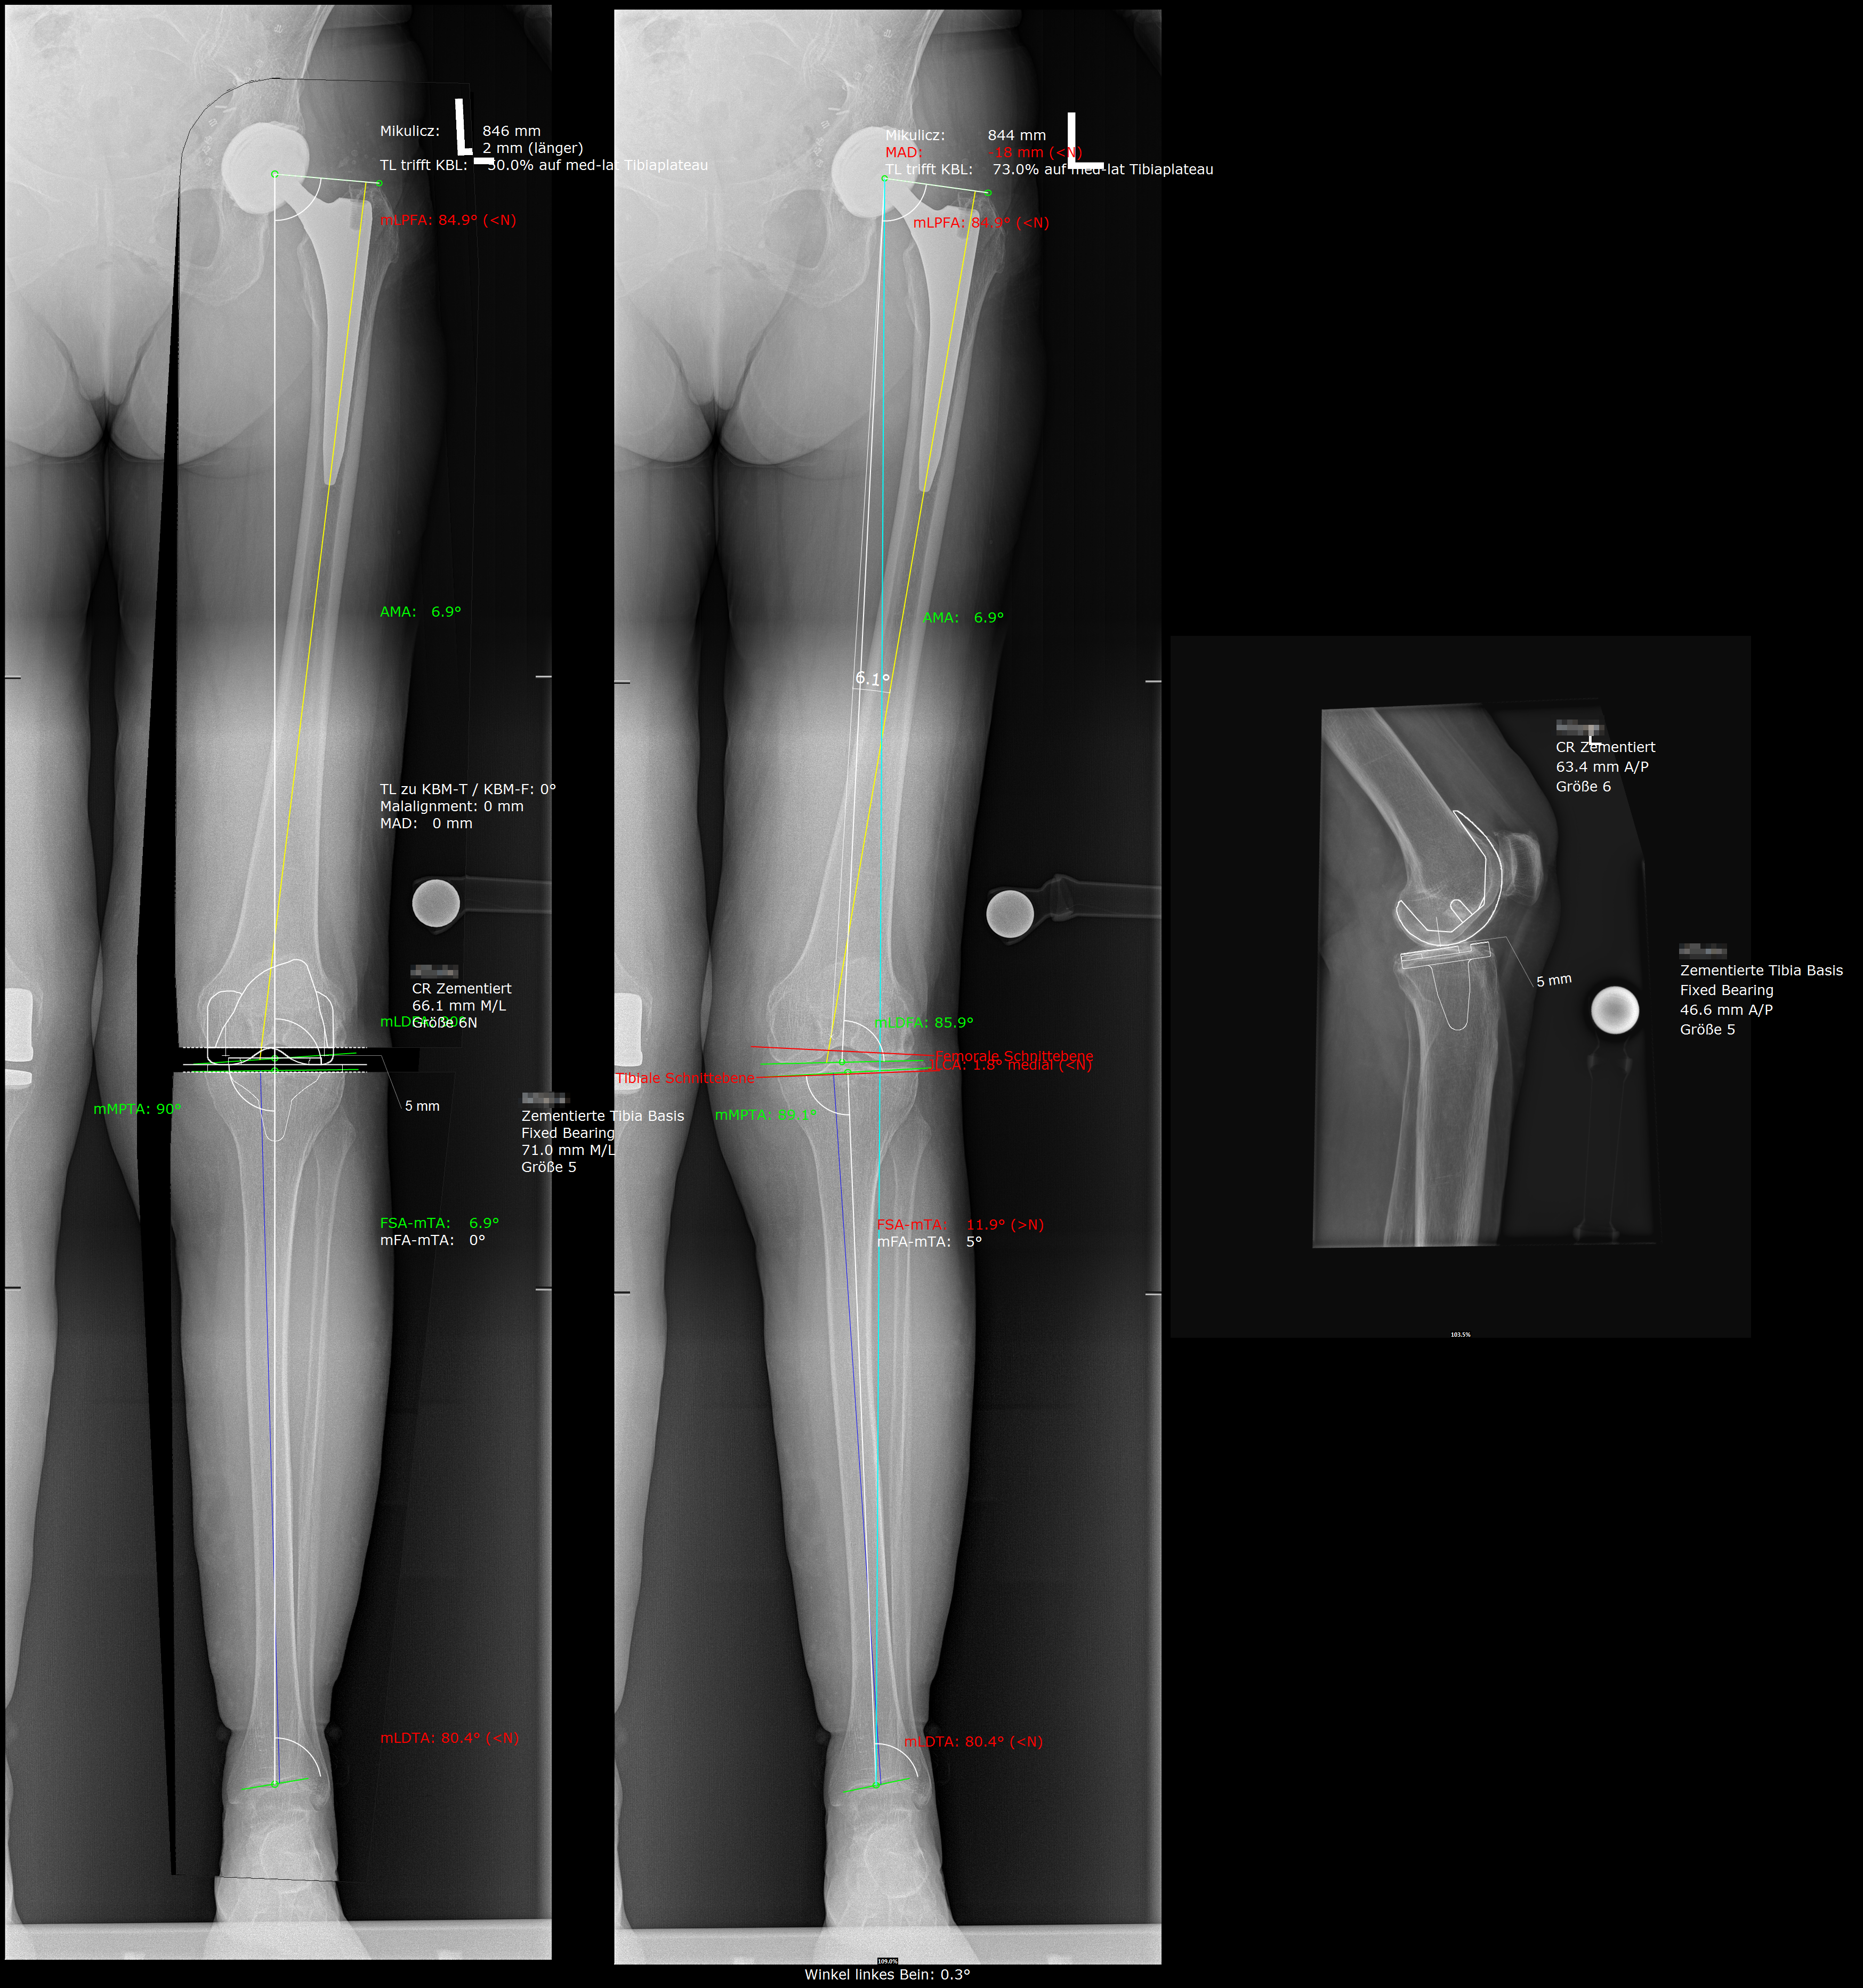

Präoperative Planung am PC

Knie-Totalendoprothese im Röntgen

Für die Ausrichtung der Endoprothesenteile gibt es im mehrere Möglichkeiten:

- Mechanische Ausrichtung (Englisch: Mechanical alignment knee arthroplasty): Die Ausrichtung erfolgt entsprechend einer geraden Beinachse. Das heißt, dass das Bein nach dieser OP annähernd gerade sein wird, was in den meisten Fällen gut funktioniert, aber nicht immer der natürlichen Bandspannung des Kniegelenks gerecht wird.

- Kinematische Ausrichtung (Englisch: Kinematic alignment knee arthroplasty): Die Ausrichtung folgt der ursprünglichen Stellung der knöchernen Strukturen. Das heißt es wird ein reiner Oberflächenersatz durchgeführt und auf eine gerade Beinachse kein Wert gelegt. Es können zwar Fehlstellungen zurückbleiben, jedoch führt die natürliche Bandspannung im Normalfall zu einer möglichst natürlichen Roll-Gleitbewegung des Kniegelenkes. Dies kann unterstützt werden durch so genannte medial-pivot Inlays. Ein Inlay ist die Plastikeinlage welche zwischen Oberschenkel-Teil (Femur-Komponente) und Schienbein-Teil (Tibia-Komponente). Diese medial-pivot Inlays sorgen für eine möglichst natürliche Knie-Beweglichkeit, da sie die natürliche Form des Schienbeins inklusive Meniskus nachahmen.

- Eine Mischung aus mechanischer und kinematischer Ausrichtung (Restricted kinematic alignment knee arthroplasty), bei der nur ein Teil der Fehlstellung belassen wird. Die genaue Ausrichung wird intraoperativ vom Operateur auf Grund der natürlichen Bandspannung des Patienten entschieden. Dadurch wird ein natürliches Bewegungsmuster des Kniegelenks bei teilweise korrigierter Knieachse erreicht.